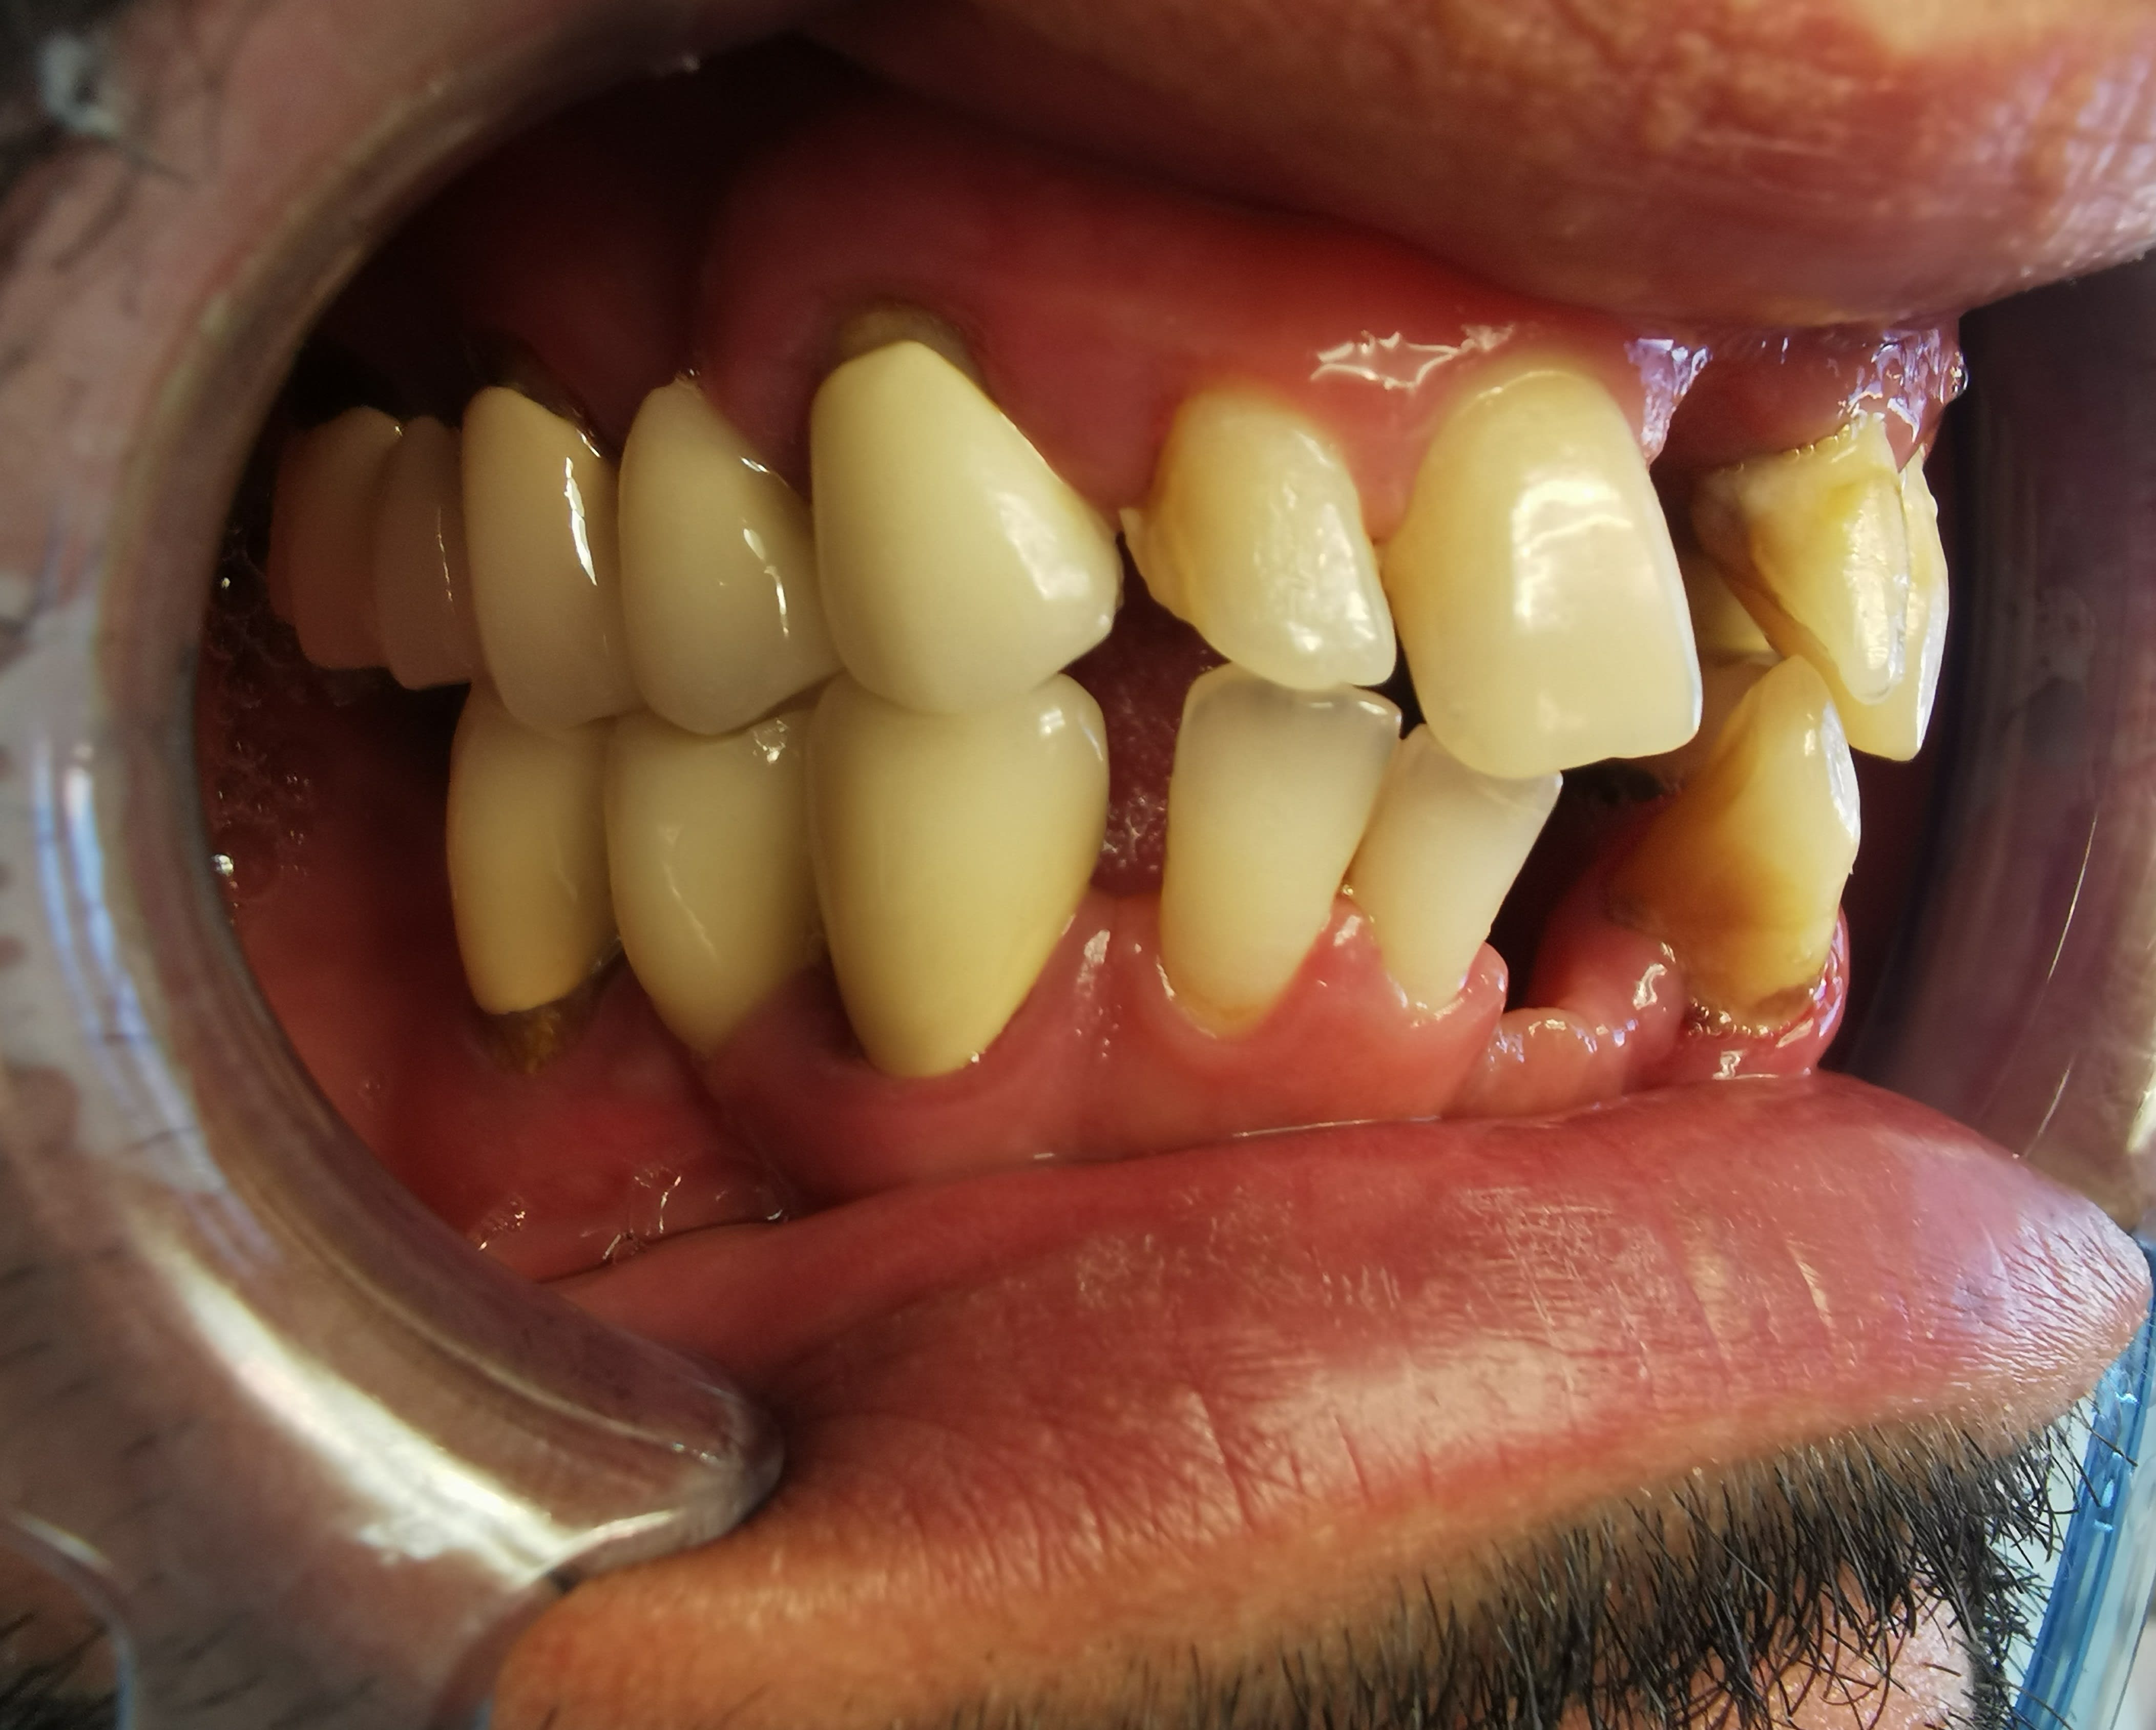

en intra buccal

Paro +++

bridge sect 1 cassé, avec mobilité ++ sur 15 et

mobilité +++ sur 22 24 et plus modérée au niveaudu bridge sect 3

Quelles dents serait il possible de conserver ?